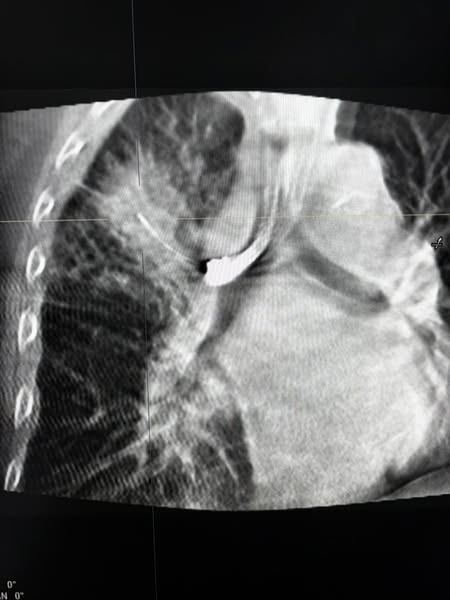

नोएडा में 9 अक्टूबर 2025 को फोर्टिस नोएडा ने फेफड़ों की कोन बीम सीटी (सीबीसीटी) निर्देशित क्रायो बायोप्सी सफलतापूर्वक करके उत्तर भारत में चिकित्सा जगत में पहली बार एक उपलब्धि हासिल की है। इस अत्याधुनिक प्रक्रिया से डॉक्टरों को एक 70 वर्षीय मरीज में फेफड़ों के कैंसर का निदान करने में मदद मिली, जिसकी स्थिति शहर के कई अन्य अस्पतालों में कई परीक्षणों के बावजूद पता नहीं चल पाई थी। यह मरीज, जो लंबे समय से धूम्रपान करता था, सांस लेने में तकलीफ और तेजी से वजन घटने की शिकायत के साथ फोर्टिस नोएडा आया था। अन्य अस्पतालों में की गई पिछली जाँचें अनिर्णायक थीं, जिनमें केवल संक्रमण या अस्पष्ट निष्कर्षों का संकेत मिला था। फोर्टिस नोएडा में एक पीईटी सीटी स्कैन से फेफड़े में एक संदिग्ध घाव का पता चला। हालाँकि, फेफड़े में छेद होने के उच्च जोखिम और अपर्याप्त या गैर-निदानात्मक नमूने प्राप्त होने की संभावना के कारण मानक बायोप्सी विधियों को खारिज कर दिया गया था,

इस मामले में कई नैदानिक चुनौतियाँ सामने आईं - ब्रोंकोस्कोपी और द्रव विश्लेषण सहित पहले के परीक्षण, अंतर्निहित कारण की पहचान करने में विफल रहे थे। यहाँ तक कि सीटी-निर्देशित बायोप्सी और रेडियल ईबीयूएस को भी अनुपयुक्त माना गया क्योंकि फेफड़े का अधिकांश भाग परिगलित (मृत ऊतक) दिखाई दे रहा था, जिससे व्यवहार्य ट्यूमर क्षेत्रों को अलग करना मुश्किल हो गया था।

इन चुनौतियों से निपटने के लिए, फोर्टिस नोएडा पल्मोनोलॉजी टीम ने, जिसका नेतृत्व पल्मोनोलॉजी के अतिरिक्त निदेशक डॉ. राहुल शर्मा कर रहे थे, सीबीसीटी-निर्देशित क्रायो-लंग बायोप्सी का विकल्प चुना, जो एक अगली पीढ़ी की, न्यूनतम आक्रामक तकनीक है जो बेहतर परिशुद्धता के लिए रीयल-टाइम 3डी इमेजिंग, उन्नत स्कोप नेविगेशन और संवर्धित फ्लोरोस्कोपी का संयोजन करती है। इस दृष्टिकोण ने टीम को क्षतिग्रस्त या परिगलित क्षेत्रों से बचते हुए फेफड़े के द्रव्यमान के जीवित भाग से सुरक्षित रूप से अक्षुण्ण ऊतक के नमूने निकालने में सक्षम बनाया।

बायोप्सी ने नॉन-स्मॉल सेल कार्सिनोमा - फेफड़ों के कैंसर का एक प्रकार - की उपस्थिति की पुष्टि की और अतिरिक्त लिम्फ नोड नमूने से कैंसर के प्रारंभिक प्रसार का पता चला। इस सटीक निदान और अवस्था निर्धारण से डॉक्टरों को अनावश्यक सर्जरी और देरी से बचने के लिए तुरंत सही उपचार योजना शुरू करने में मदद मिली।